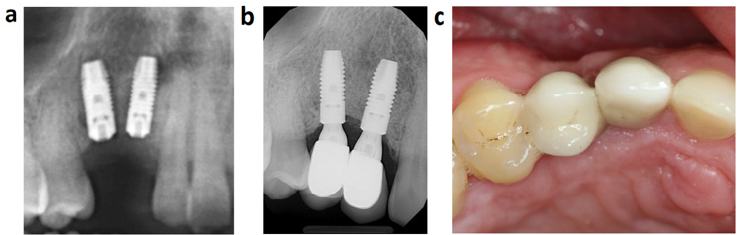

After 3 months the cranial part of the odontoma was placed near to the occlusal plate and it could be easily removed via a second operation. During the exposure of the odontoma remnant a buccal bone ridge was preserved to minimalize the bone loss (Figure 3a). Thorough excochleation was performed and the complete removal of tumor was confirmed by radiological examination. The bone defect was filled with bone allograft particles coated with albumin and gentamycin (Figure 3b). Antibiotics were prescribed after both surgeries; amoxicillin/clavulanic acid 875/125 mg 2 times a day for one week. Adverse reactions were not experienced during the healing period. After 6 months the radiographic image showed complete graft integration and bone remodeling (Figure 3c). The next step of treatment was the implant placement. An L-shaped flap was prepared similarly like at the time of odontoma removal. The clinical findings confirmed a complete bone healing; the examined area was appropriate for implant placement without further bone augmentation. Two Astra 4,0 * 11 mm dental implants were placed which had 25 Ncm primer stability (Figure 4a). After a 3-month healing, the implants were exposed and two porcelain—fused-tometal crowns were fixed with cement in one piece. After a threeyear follow up the crown-mucosa junction was intact and less than 1mm bone loss could be observed (Figure 4b&4c).

Figure 4: Tooth restoration

a. Radiographic image after the implant placement.

b. Radiographic image at 3-year control.

c. Oral status at 3-year control.